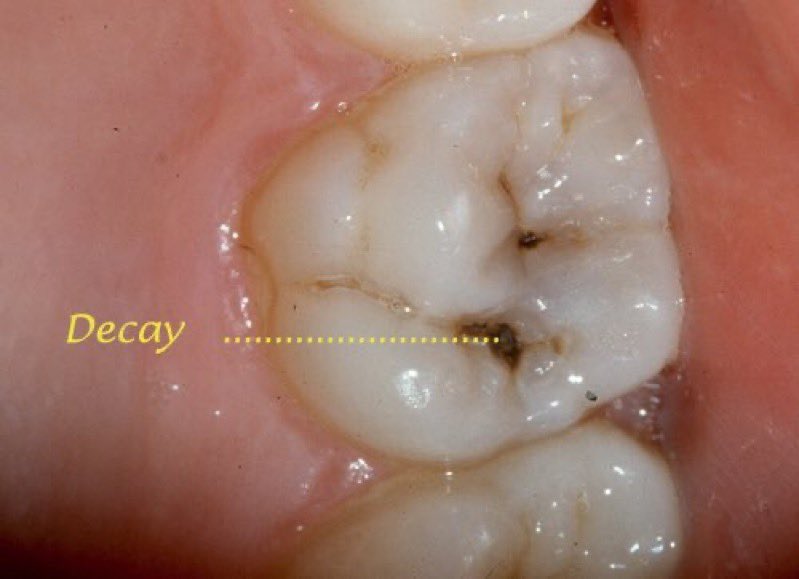

٦/ التسوس الظاهر:

عند ملاحظة تغير في لون السن مهما كان، لابد من مراجعة الطبيب لعمل اللازم